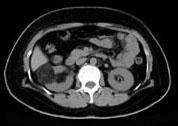

问题 男,55岁,因右腰部不适1 年余,行CT扫描如图所示,下列说法正确的是 ( )

选项 A、考虑为右肾癌 B、考虑为右肾错构瘤 C、其内见低密度脂肪影 D、其边缘清楚,与周围境界清晰 E、右肾中极可见一类圆形肿块影,肿块密度不均

答案 BCDE